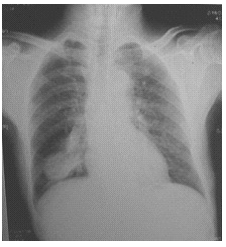

思路:看胸片重要內(nèi)容是胸廓情況→氣管情況→肺紋理情況→肺門(部位)是否有異常陰影→縱膈是否居中→心影大小→膈面→肋膈角

胸廓對稱,氣管居中。雙側肺紋理走向規(guī)則,左肺門旁見一斑片狀密影,與左肺門相連,余肺野清晰,未見明確病變;雙肺門稍增濃,縱膈居中,心影大小形態(tài)正常;雙側膈面光滑,肋膈角銳利醫(yī)學|教育網(wǎng)。